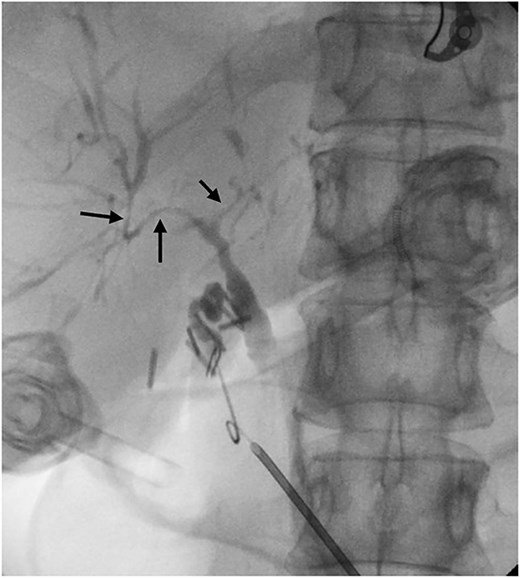

Six months after surveillance imaging, she was presented with ongoing abdominal pain. Liver function tests (LFTs) and Ca 19–9 remained normal at this time. A repeat abdominal US demonstrated an irregular gallbladder wall with thickening up to 5 mm and two stable gallbladder polyps, the largest measuring 7 × 8 mm (Fig. 2). Due to ongoing symptoms and changes on imaging, a laparoscopic cholecystectomy with intraoperative cholangiogram was performed without complication. At the time of surgery, the gallbladder was noted to have an area of wall thickening thought to be a Phrygian cap. The operative cholangiogram was consistent with PSC, with narrowed intrahepatic ducts observed (Fig. 3).

Intraoperative cholangiogram demonstrating intrahepatic duct stricturing (arrows) consistent with PSC.